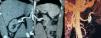

A pesar de tratamiento hipotensor intravenoso (labetalol y nitritos) mantuvo cifras elevadas de TA, por lo que se decidió ingreso en la Unidad de Cuidados Intensivos con inicio urgente de hemodiálisis aguda y plasmaféresis, simultáneas. Se practicó fondo de ojo, con resultado compatible con retinopatía hipertensiva de grado iv. La ecografía renal evidenció unos riñones desestructurados con mala diferenciación córtico-medular y una asimetría evidente. La angio-TAC (fig. 1) permitió descartar una estenosis de arteria renal izquierda, pero puso de manifiesto un aneurisma en dicha arteria de 2cm de diámetro con pared calcificada y trombosada. El ECG mostraba signos de hipertrofia ventricular izquierda y sobrecarga diastólica y la ecocardiografía, una hipertrofia concéntrica severa de VI con función sistólica conservada.